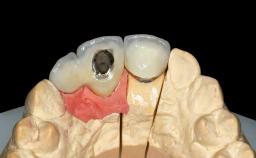

Replacement of Four Incisors with a Fixed Partial Denture on Two Narrow-Neck Implants after Implant Failure

| Type of Implants | One-Piece|Reduced-Diameter |

| Prosthesis Type | FDP |